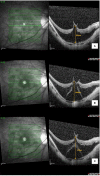

Case presentation: An elderly female patient with bilateral high myopia and pre-existing myopic foveoschisis underwent uncomplicated sequential cataract surgeries 2 weeks apart. She was able to achieve a satisfactory visual outcome for her left eye with stable myopic foveoschisis and visual acuity of 6/7.5, near vision N6. However, her right eye vision remained poor postoperatively, with a visual acuity of 6/60. Macular optical coherence tomography (OCT) revealed a new right eye outer lamellar macular hole (OLMH) and outer retinal detachment (ORD) within pre-existing myopic foveoschisis. Her vision remained poor after 3 weeks of conservative management, and she was offered vitreoretinal surgical intervention with pars plana vitrectomy, internal limiting membrane peeling, and gas tamponade. However, she refused surgical intervention, and her right vision remained stable at 6/60 over 3 months of follow-up.